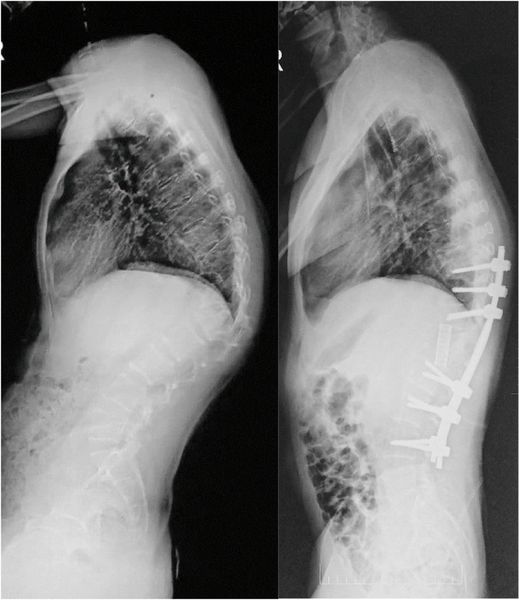

![Поражение позвоночника при туберкулёзе [13] Поражение позвоночника при туберкулёзе [13]](/media/bolezny/tuberkulez-pozvonochnika/porazhenie-pozvonochnika-pri-tuberkulyoze-13_s_gilAZkF.jpeg?dummy=1756197621905)

Поражение позвоночника при туберкулёзе [13]

- Лечебно-вспомогательные операции. Проводятся, чтобы восстановить опорную функцию позвоночника, скорректировать его искривление, устранить вторичные осложнения и последствия болезни [11]. Применяют мобилизующие и стабилизирующие операции, например транспедикулярную фиксацию (ТПФ), при которой позвонки закрепляются в правильном положении с помощью металлических винтов. Также могут выполнять абсцессотомию (вскрытие и дренирование туберкулёзных абсцессов) и фистулотомию (удаление образовавшихся свищей) [12].

![Транспедикулярная фиксация позвоночника [15] Транспедикулярная фиксация позвоночника [15]](/media/bolezny/tuberkulez-pozvonochnika/transpedikulyarnaya-fiksaciya-pozvonochnika-15_s.jpeg?dummy=1756118214348)

Транспедикулярная фиксация позвоночника [15]